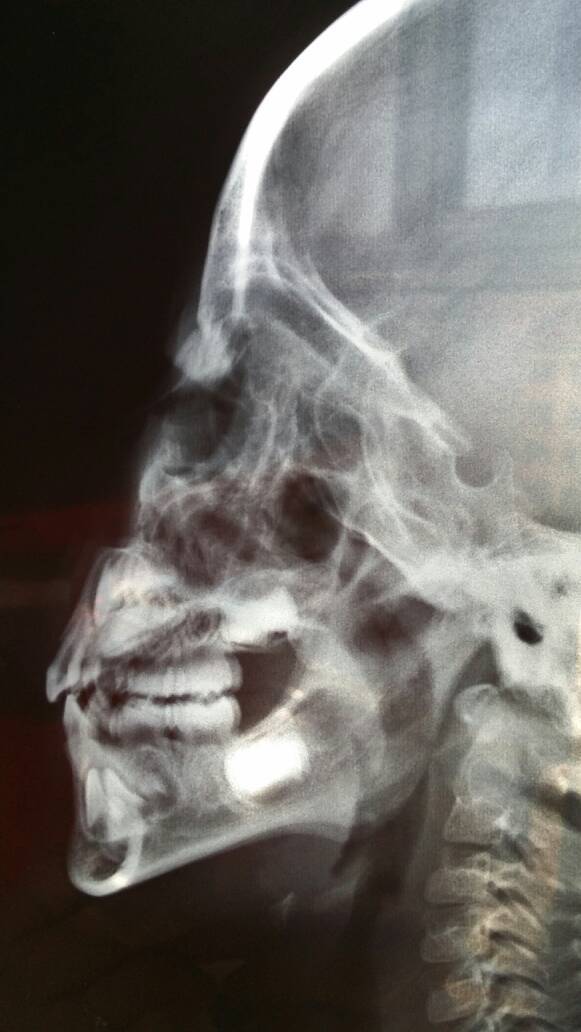

四岁小孩鼻炎,拍的片子,不知道严重不严重! 点击展开 匿名用户 2014-11-09 09:55 为您推荐: 其他回答 您好;鼻炎主要症状有鼻塞,流涕,打喷嚏,头痛,头昏等。临床表现在白天、天热、劳动或运动时鼻塞减轻,而夜间或寒冷时鼻塞加重. 在医生的指导下服用香菊片鼻炎宁罗红霉素治疗。同时注意多喝水,避免受凉,预防感冒 张丽医师 2014-11-09 10:03 相关问题 小孩得了鼻炎拍片子对身体有坏处吗? 得鼻炎的小孩出现什么反映? 我姐五个月小孩鼻塞怎么办?她说鼻塞好久了,会不会是鼻炎呀?